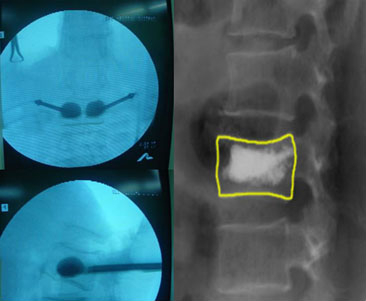

척추성형술 수술 후 사진

골다공증성 척추골절에 시행한 척추성형술

골다공증성 척추골절에 시행한 척추성형술 수술 전/후 X-ray

수술 전

수술 후